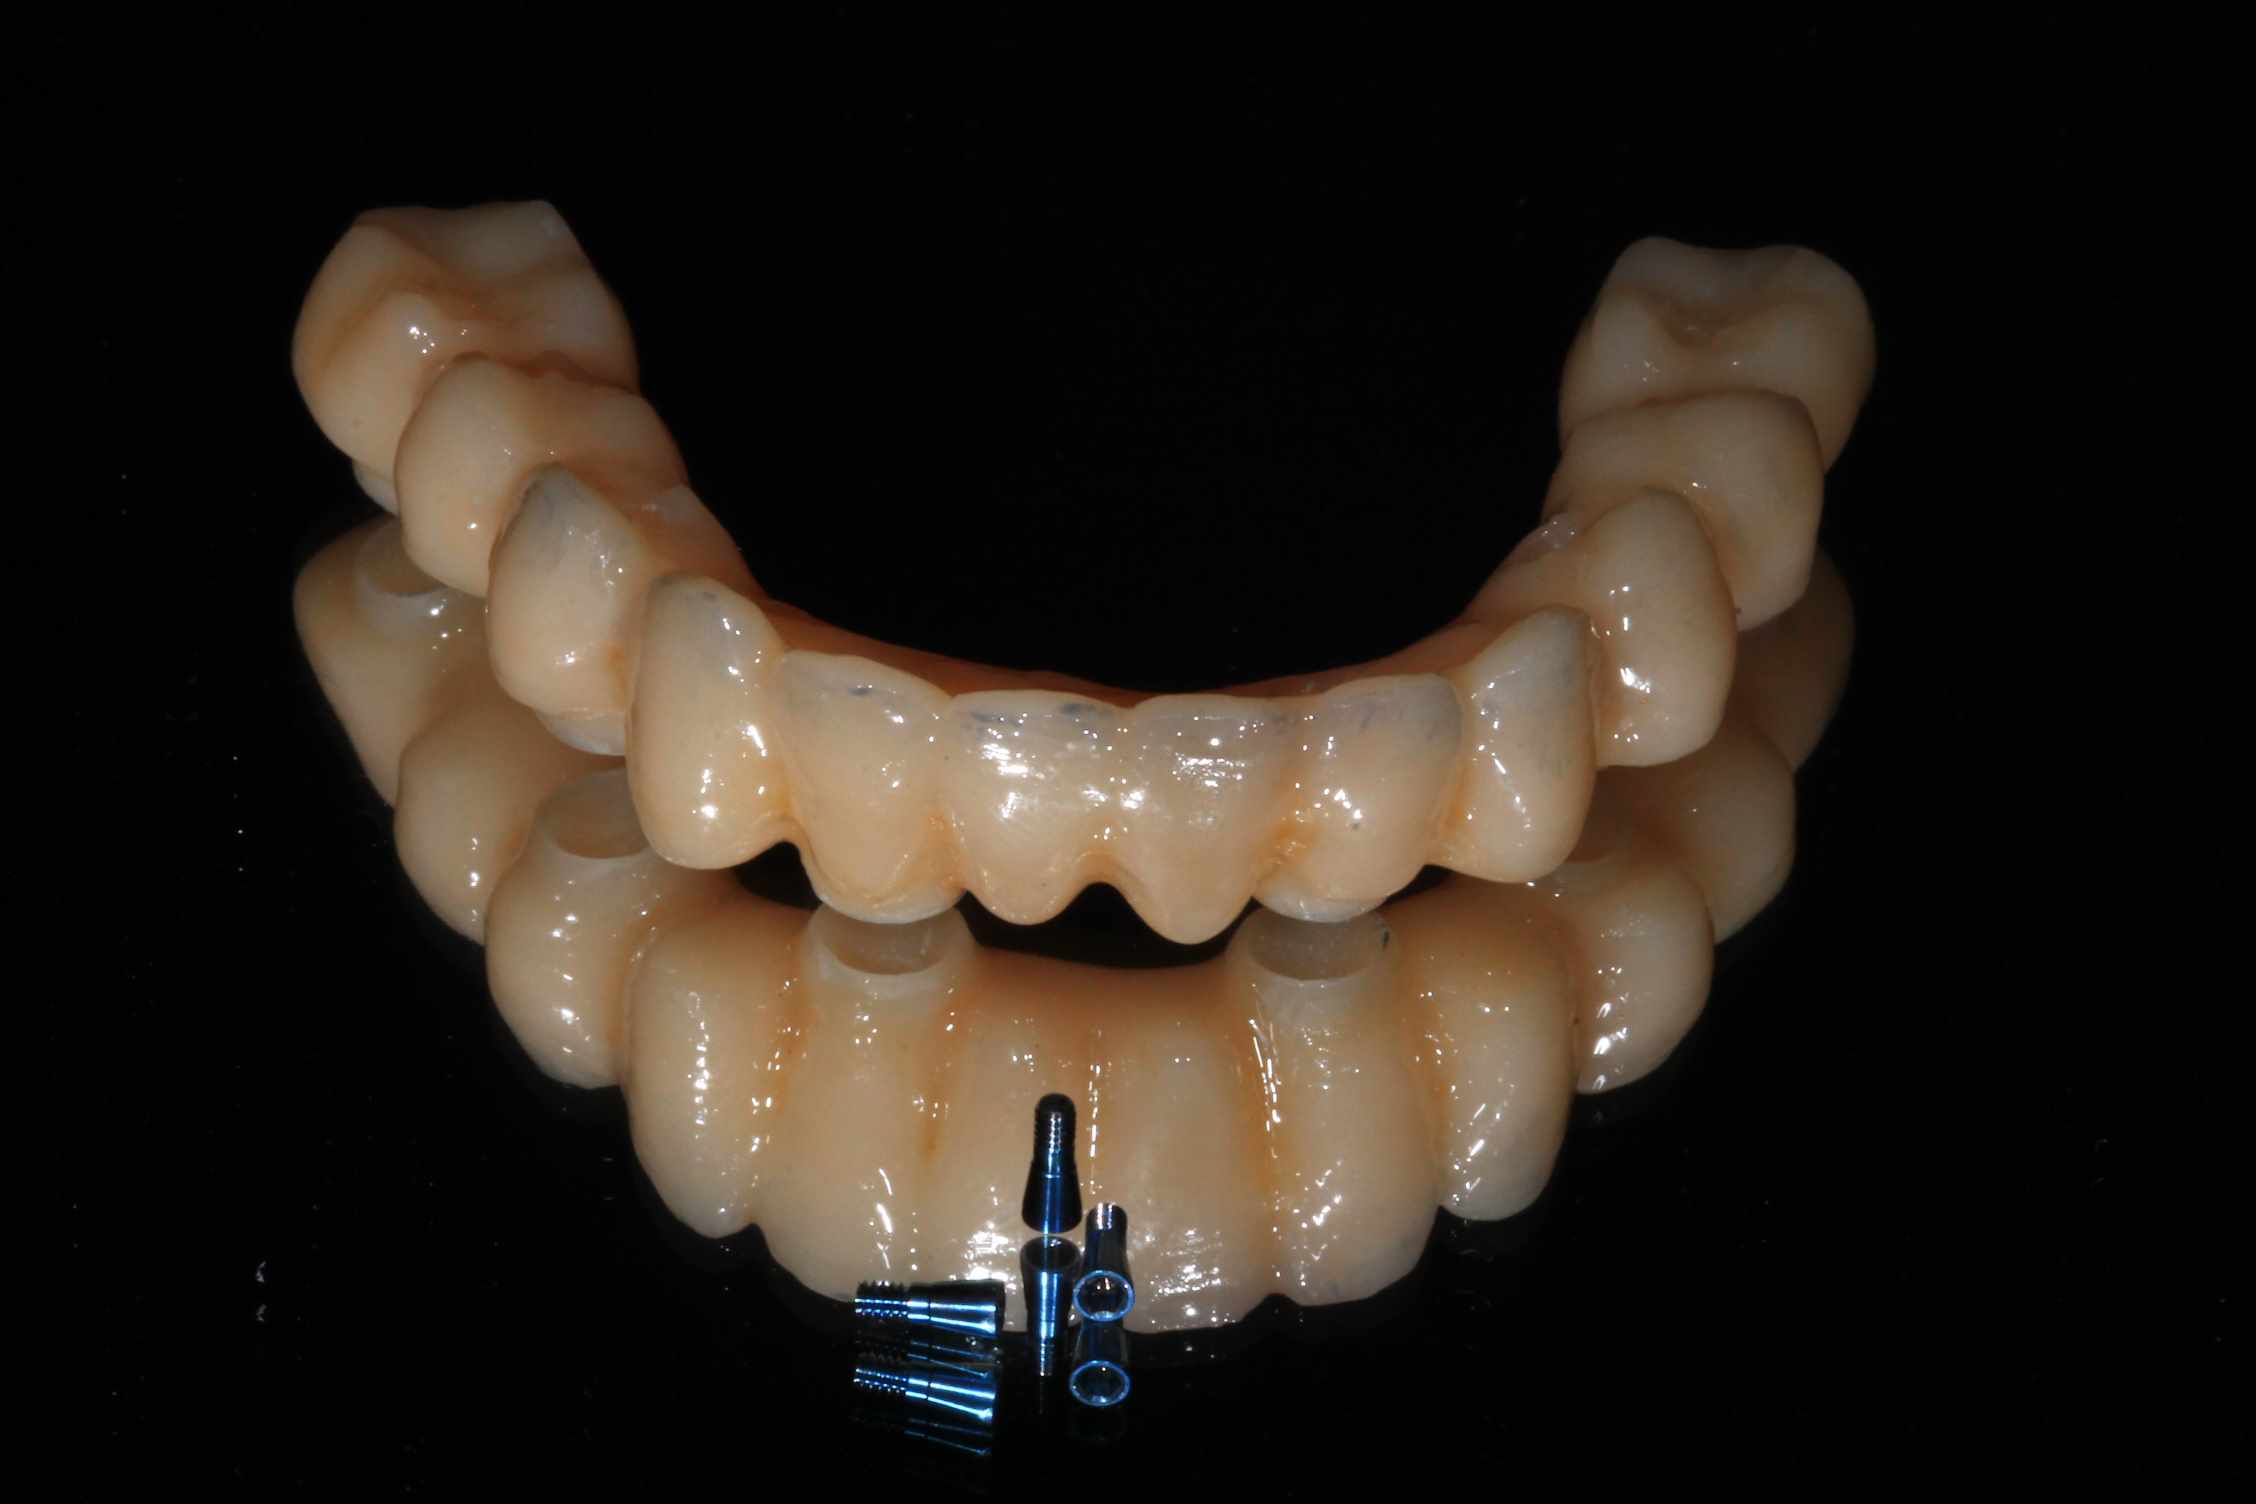

Bridge immédiat posé dans la continuité de la pose des implants

Uya2oirluigh1vu3fex4y70uezce - Eugenol

Tu me demande les photos du cas et ton seul commentaire est de poster une photo de ton provisoire :)

Pour montrer qu'il est plus joli que le mien ? Et bien c'est vrai, je le trouve pas mal.

Cas bi-max réalisé selon le protocole de Dimitri, entierement délégué, pour une fois, a vivien, laboratoire LIO. Planif et guide réalisé avec Co-diagnostic, bridge prov PMMA rosenscrew réalisé en amont de la chirugie.